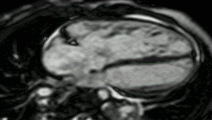

Myocardial infarction. Imaging in the 4-chamber plane. Left: Inversion recovery LGE sequence. Right: Corresponding cine sequence. This shows a chronic infarction with akinetic apex and transmural scar. Mitral regurgitation is also present.